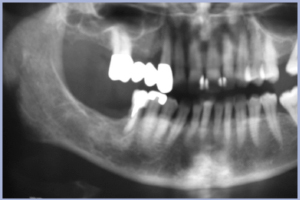

Il secondo case report (già pubblicato con un controllo ad 1 anno nell’Exacone® News n° 6) è inerente a una paziente donna di 66 anni trattata nel 2004 per una edentulia parziale intercalata al primo quadrante, conseguente ad estrazione di elemento 13 pilastro di protesi, per patologia parodontale non trattabile (Figg. 8, 9). Il piano di trattamento prevede una protesi a ponte di tre elementi implanto-supportata 15-13. Si mantiene l’elemento 16 come pilastro di sostegno della protesi preesistente per tutto il periodo della guarigione. Si pratica una chirurgia con lembo e si esegue una preparazione osteotomica dei due siti. In sede 15 si esegue la tecnica BAOSFE (Bone-Added Osteotome Sinus Floor Elevation) secondo Summers: l’altezza ossea è di circa 8 mm e si posiziona un impianto 4,1×10 mm. In sede 13 si posiziona un impianto 4,1×12 mm con tecnica OSFE (Osteotome Sinus Floor Elevation) (Figg. 10, 11). L’osso è di qualità 3, la stabilità primaria è buona. La sede 13 presenta ipotrofia verticale ed orizzontale (pregressa lesione parodontale) e quindi si pratica una GBR mediante membrana “Goretex” fissata con due chiodini.

A 5 mesi si effettua il rientro e si rimuove la membrana: si apprezza un ripristino dei volumi prima mancanti (Fig. 12). Dopo la guarigione dei tessuti molli si può finalizzare protesicamente il caso (Figg. 13, 14). Si rileva una integrità dei tessuti duri e molli ed una corretta integrazione estetica del manufatto nell’ambito del cavo orale. Abbiamo rivisto la paziente nel 2012, a distanza di 8 anni: il risultato si è mantenuto nel tempo, i tessuti appaiono sani ed i volumi sono sovrapponibili al tempo “0” (Fig. 15). La radiografia mostra un mantenimento del livello osseo sovrapponibile al quadro iniziale (Fig. 16). La soddisfazione della paziente è la nostra soddisfazione.

- Figg. 8, 9 – Quadro clinico-radiografico iniziale (anno 2004): fallimento protesico al primo quadrante per parodontite grave complicata al pilastro 13, non recuperabile

- Fig. 11 – Immagine radiografica post-operatoria dell’intervento implantare

- Fig. 16 – Immagine radiografica al controllo dopo 8 anni (anno 2012). Mantenimento dei livelli ossei. Stabilità ossea nel tempo